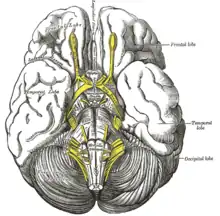

Base du cerveau.